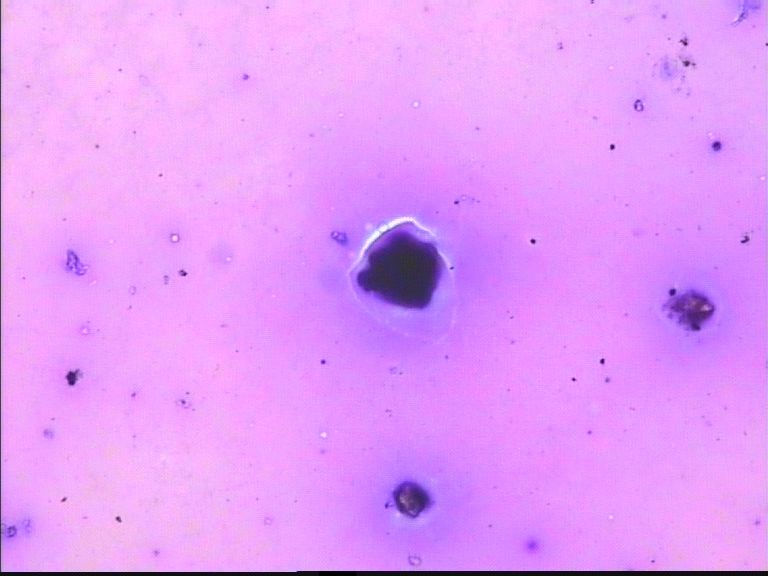

67岁胸水,有风湿病

• 67岁胸水,有风湿病图3

图3

没看出有设么异常细胞   图20好像有霉菌菌丝

深的可能是染料渣子

深染的东西像杂质

这些深染的是什么东西呢?好奇怪

制片质量欠佳,直接就看不出是什么了!

看不清,不能诊断

深染的不是细胞(就是细胞,看不到结构,也不能诊断)。